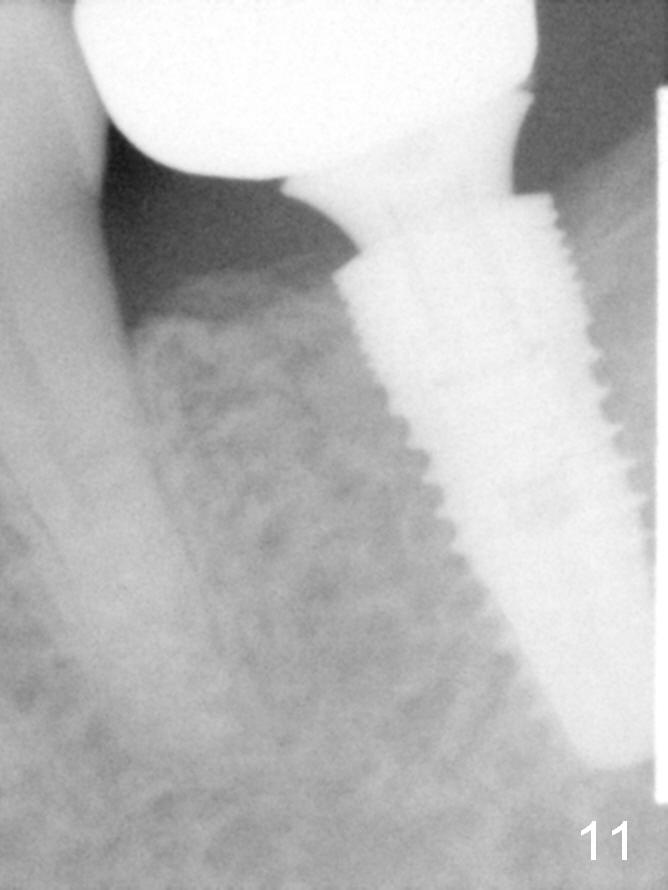

A 48-year-old lady is a dental phobic, requesting extraction of the lower left 2nd molar (Fig.1).   She returns for implant placement 9 months post extraction (Fig.2).  The ridge is mildly to moderately atrophic.  It appears that a 5x12 mm implant is appropriate for the site (Fig.3).  For safety, osteotomy is initiated at the depth of 10 mm; it appears that there is enough height for a 12 mm implant (Fig.4).  The depth is controlled by drill stopper (Fig.5 S).  Finally a 5x12 mm implant is apparently safely placed (Fig.6).  A healing abutment is placed and the incision is sutured with 4-0 Chromic gut (Fig.7).  Perio dressing is applied around the healing abutment for wound protection (Fig.8).  It appears that the healing abutment (Fig.8': *) helps stabilize the perio dressing, which remains in place 1 week postop.  When the perio dressing is removed, the wound around the healing abutment is healing (Fig.9).  There is no bone loss around the implant 3 months postop (Fig.10 (H: healing abutment), or 16 months postop (i.e., 9 months post cementation, Fig.11,12).  The patient complains of pain when she chews with the implant crown, but pain stops whenever she does not bite.  Percussion does not elicit any discomfort.  The gingiva is healthy.  There is possibility of the buccal plate being thin or the lingual plate being perforated in the submandibular fossa.  If the discomfort remains the same next 6 months, CBCT will be prescribed.